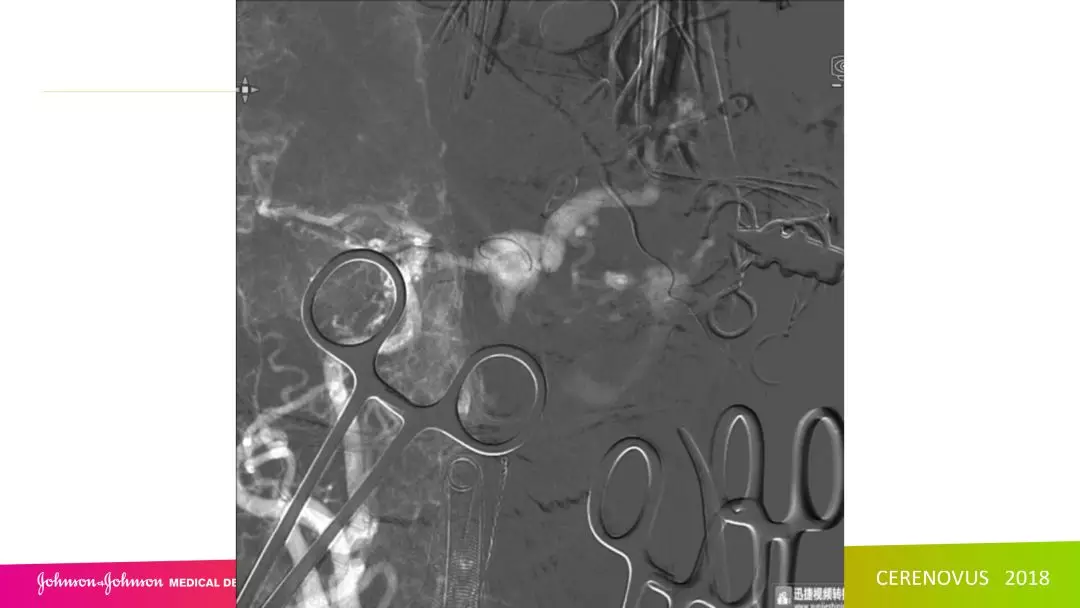

复合手术治疗海绵窦区硬脑膜动静脉瘘一例